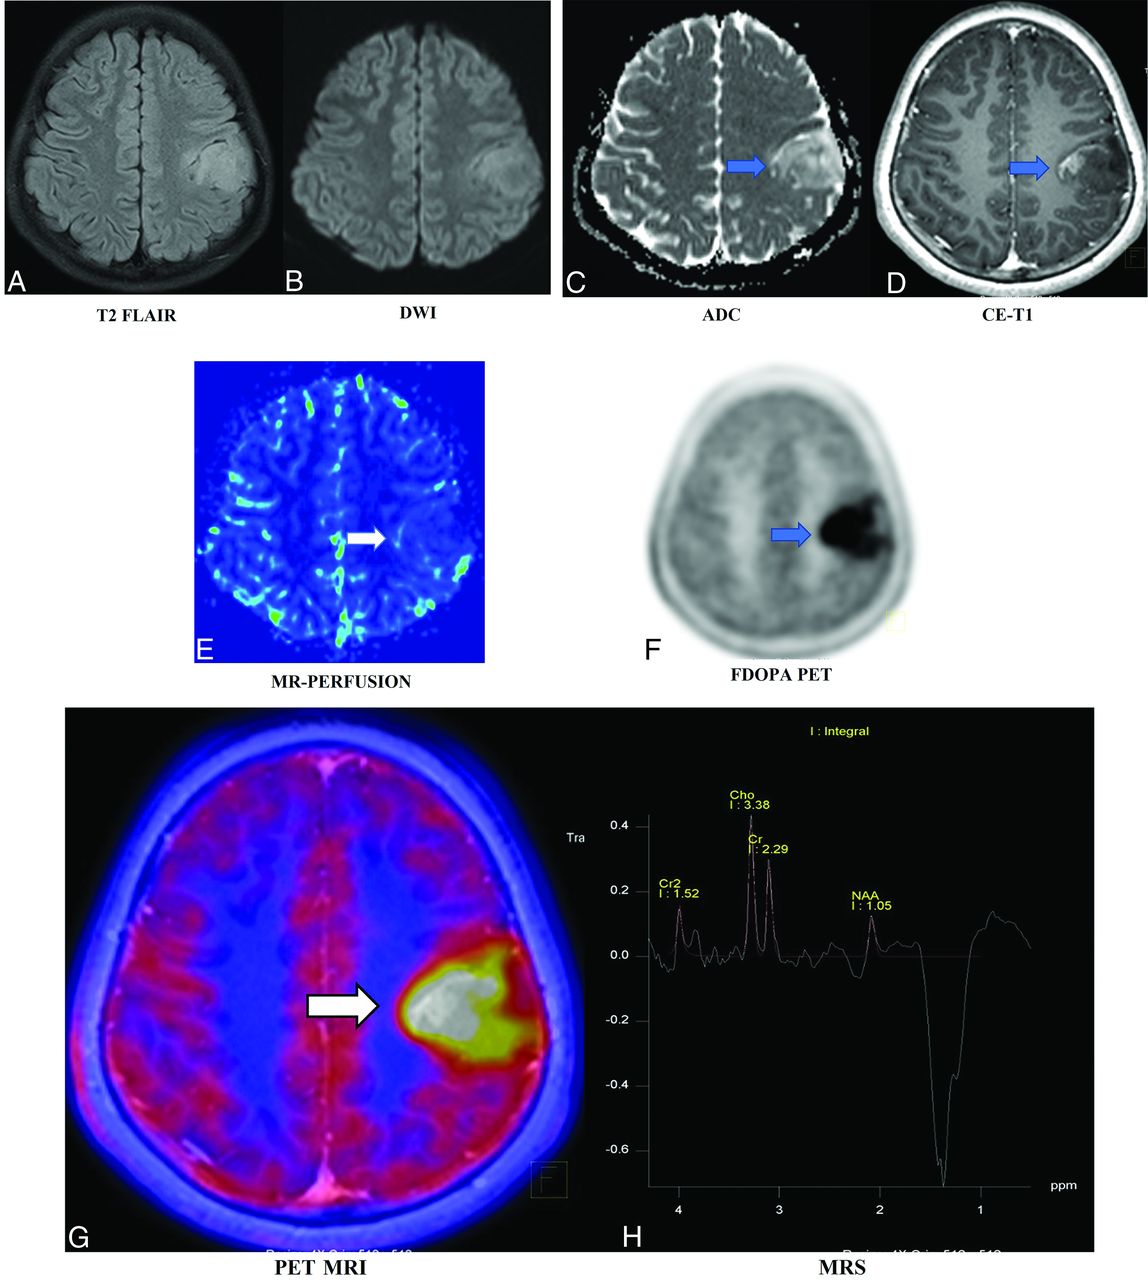

A 37-year-old man with a known diagnosis of oligodendroglioma, status post resection and chemoradiation. Postcontrast T1-weighted image (A, blue arrow) shows a recurrent enhancing lesion along the inferomedial aspect of the resection cavity of the right frontal region involving the body of the corpus callosum. Fused-PET MR images (B and C) show intralesional increased FDG slightly higher than in the white matter and lower than in the gray matter with increased rCBV perfusion (D, white arrows). Fused FET-PET MR images (E and F) show a relatively larger volume of a recurrent lesion, allowing better estimates of the extent of the lesion. Multivoxel MRS (G) shows an increased choline peak and decreased NAA peak. The pathologic diagnosis was a recurrence. This case highlights the superiority of AAT over FDG, congruent findings on MR imaging and FET-PET, and an excellent TBR, which were helpful in radiation therapy planning and re-surgical resection. CE indicates contrast-enhanced.